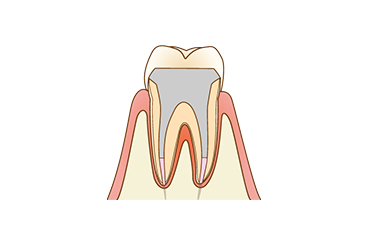

【6】歯の土台装着

虫歯の進行によって削ってしまった歯を補うために、歯の土台を入れたうえで被せ物を装着します。